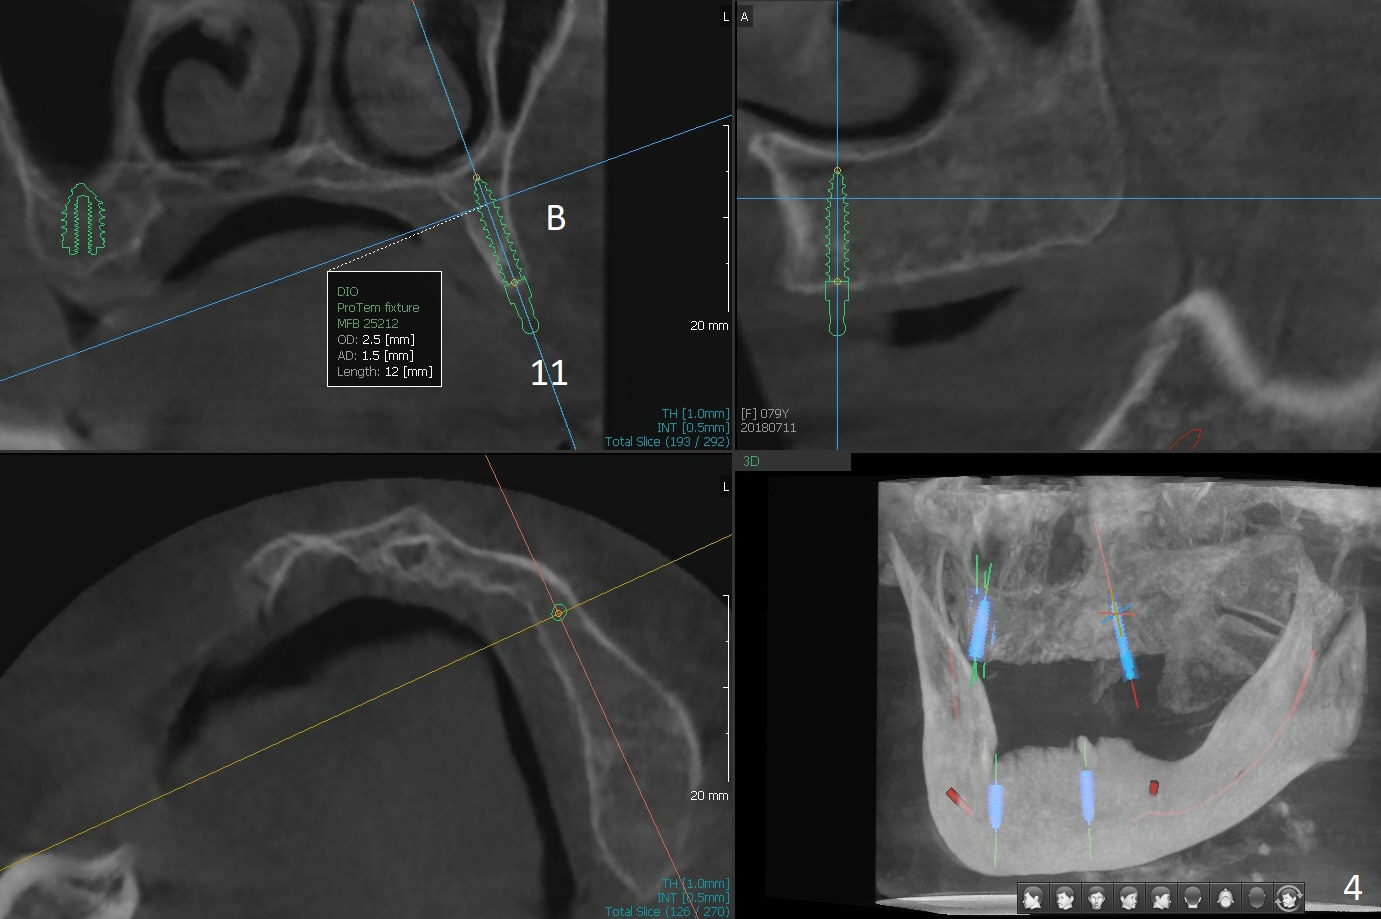

A 80-year-old woman wants to correct cross bite of complete dentures (Class II relationship). It seems that implant supported overdentures can make it possible (retention). Six implants will be placed in the maxillary canine and 2nd premolar and 2nd molar areas with surgical guide (Fig.1-6 (anterior ridge narrow)). Bone density is low. Prepare soft reline.